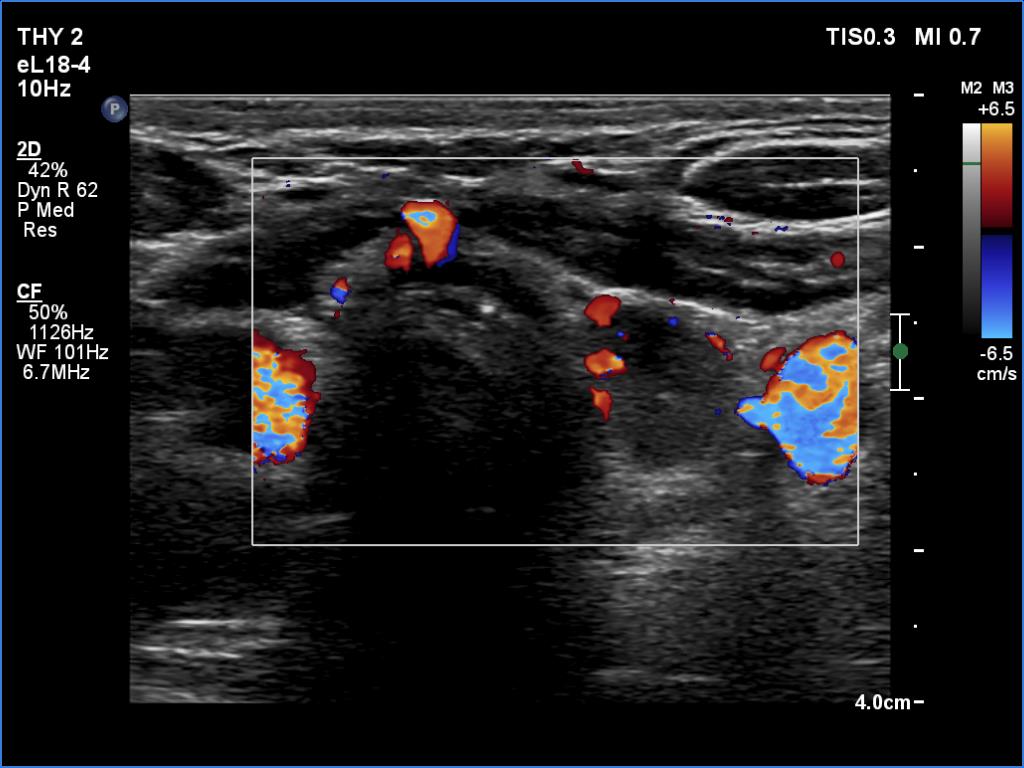

First examination (1st to third rows of images):

Ultrasonography revealed a hypoechogenic nodule in the ventromedial part of the left lobe. The nodule had irregular borders, contained microcalcifications and displayed perinodular and irregular intranodular blood flow.